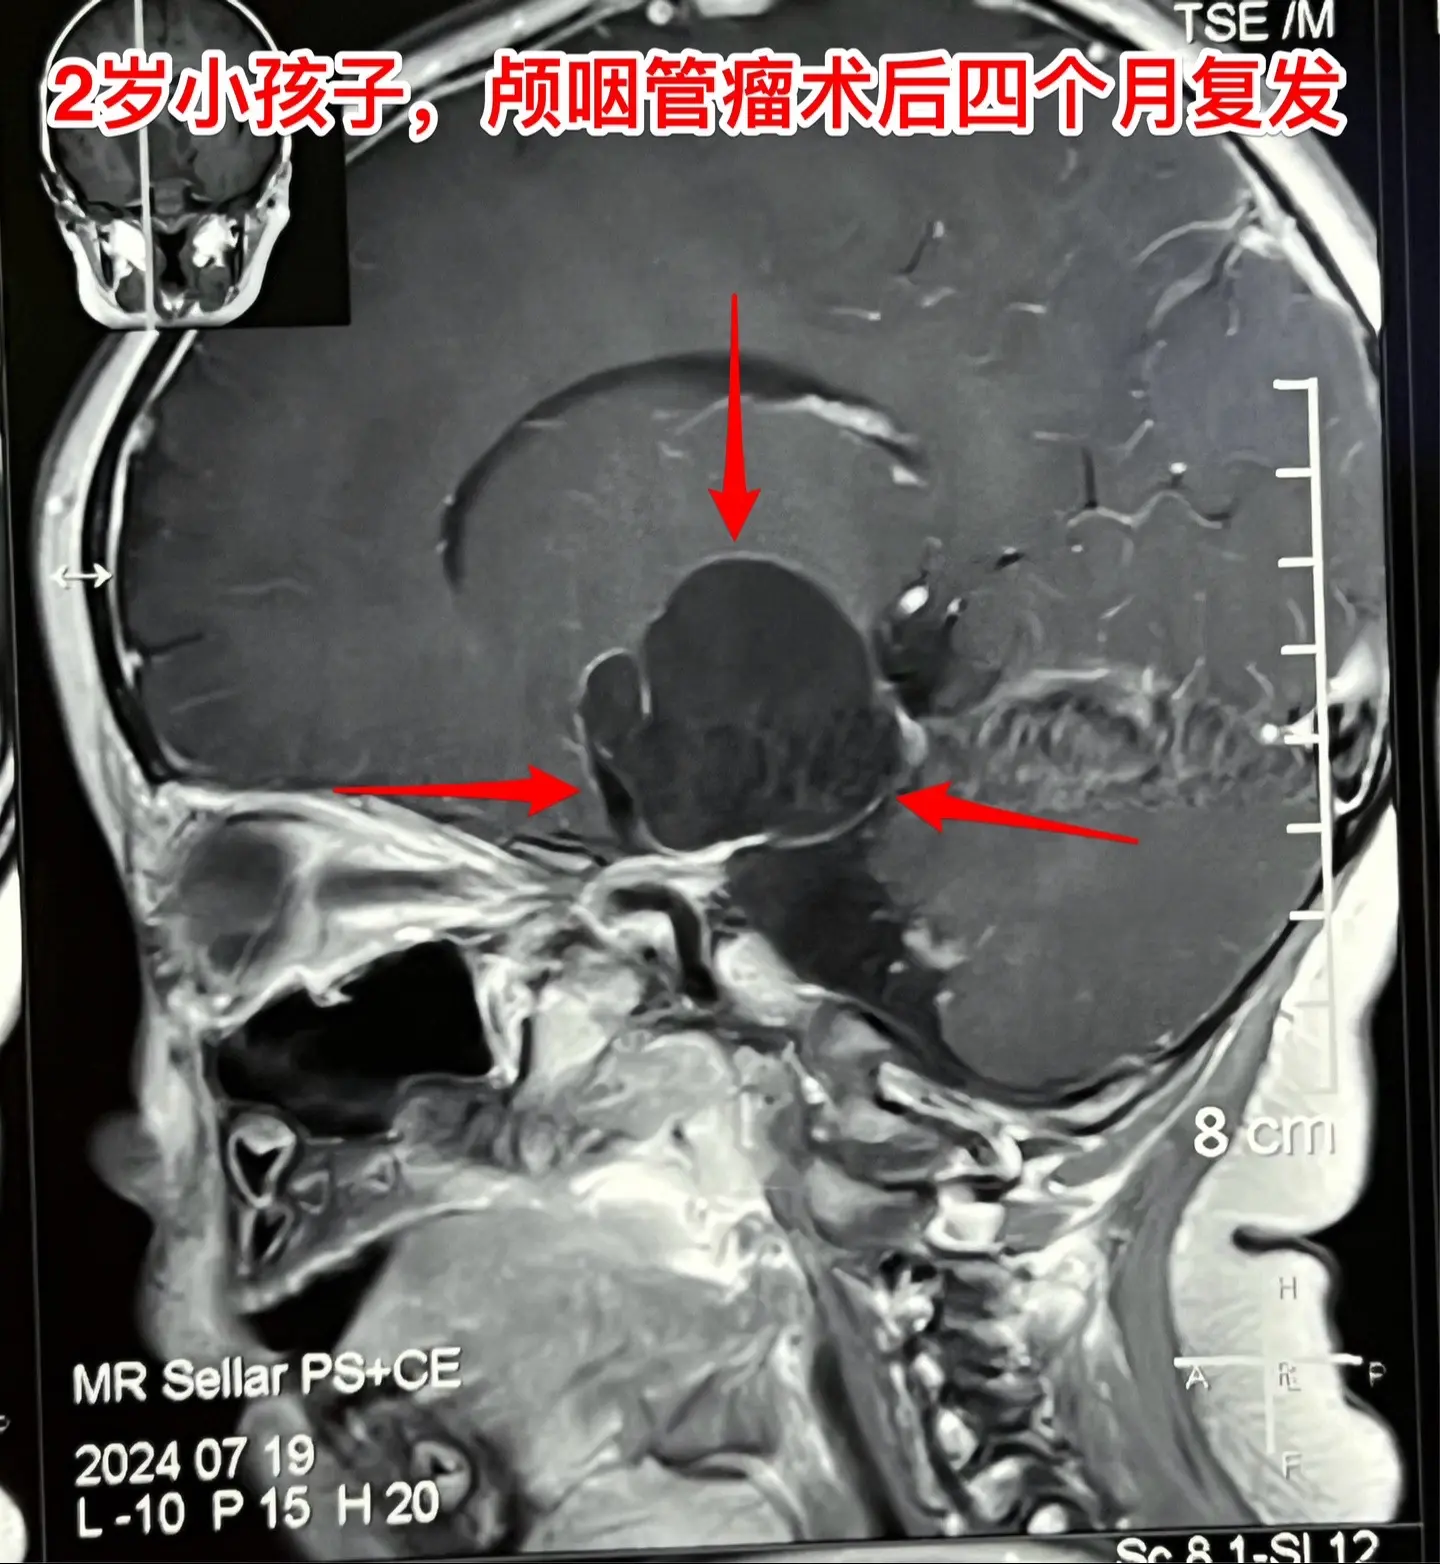

2岁孩子颅咽管瘤复发不得不接受手术。2岁多的山东女孩子,在颅咽管瘤手术后4个月(在山东省作的)发现右侧眼睑下垂越来越严重。复查磁共振显示颅咽管瘤复发了,肿瘤体积很大,患儿的左侧上下肢活动力量也变差了。 八月八日小朋友接受了人生中的第二次开颅手术。手术过程很顺利,也很艰难。一部分肿瘤囊壁菲薄,与周围血管粘连紧密,花费很长时间才讲肿瘤完全切除。 手术后患儿很快就清醒了,能说话,四肢都能活动。希望她能顺利出院。